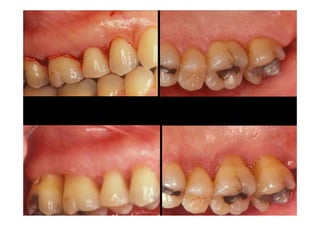

SUBGINGIVAL

CURETTAGE

BEFORE AND

FOUR WEEKS

AFTER

PROCEDURE